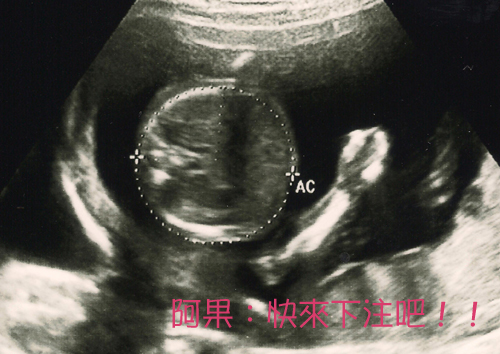

Rachel:◆ 提示2:35w+1產檢阿果重2350g

elaine_wu: 這是週數小時醫生給的,最近幾次拿到的照片都是圓圓的一陀東

(頭或腹部),妳產檢都沒有給照片的嗎???